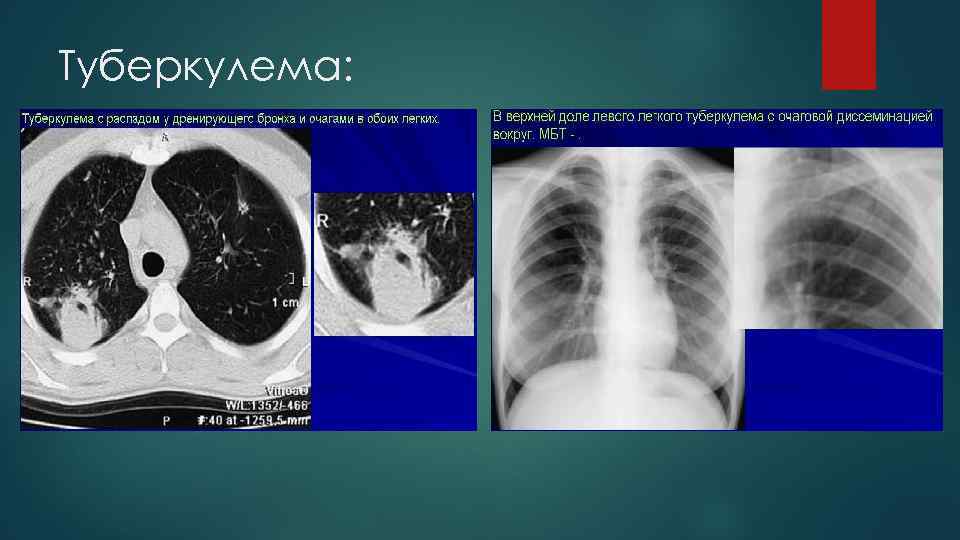

Туберкулема:

Методы лучевого исследования Рентгенография Линейная томография КТ Хронический очаговый туберкулез - представлен икапуслированными, четко отграниченными казеозными очагами или конгломератами очагов, частично кальцинированными или фиброзированными, бронхоэктазами и эмфиземой - характерны внутридольковые очаги и бронхоцелле Инфильтративный туберкулез легких - ограниченное затемнение легочного поля, обычно с нечеткими контурами разнообразной формы и локализации в виде облаковидного или круглого инфильтрата, сегментарного или долевого поражения ( перициссурита с инфильтрацией легочной ткани вдоль междолековых щелей - свойственны очаги распада и очаги отсева Туберкулема - тень неправильной округлой формы с неровными, но четкими контурами, возможны плотные включения (обызвествления) и участки просветления (полости деструкции), а вокруг нее – очаговые тени отсева. - КТ с контрастным усилением: отсутствие повышения плотности патологического очага - различают гомогенную, слоистую и конгломератную, что позволяет дифференцировать их от неистинных туберкулем инфильтративно-пневмонического